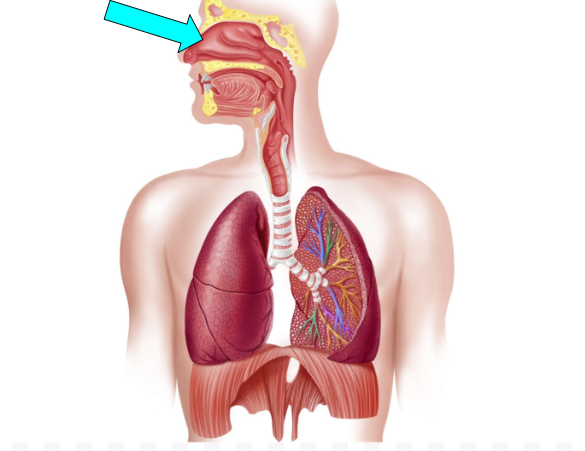

Nasal Cavity (pic)

Oral Cavity (pic)

Frontal Sinus (pic)

Sphenoidal Sinus(pic)

Pharynx (pic)

Epiglottis (pic)

Larynx (pic)

Trachea (pic)